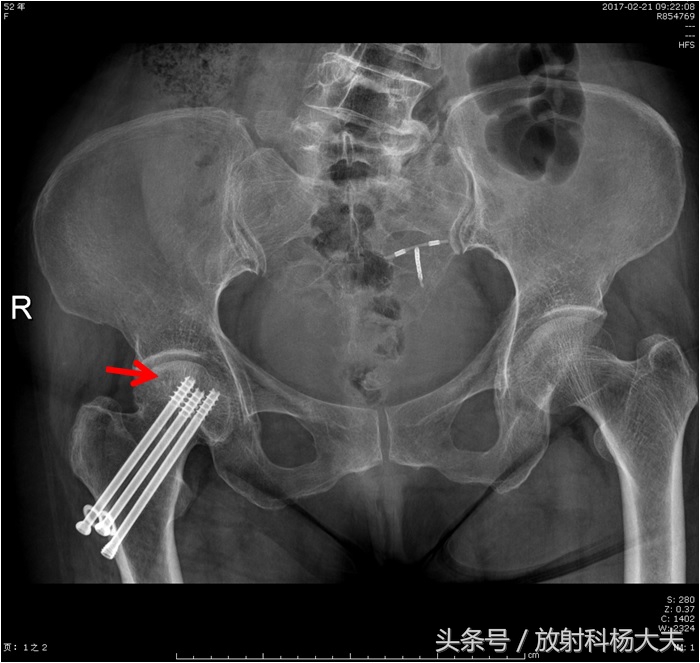

保守治疗,约一年后复查,这次又拍了X光片。

这个人为何会在股骨颈骨折术后发生坏死呢?其实这是股骨颈骨折的一个常见的继发改变。骨折后是否发生股骨头坏死(AVN)主要取决于血管损伤程度,还取决于血运重建情况,能否在股骨头塌陷之前恢复足够的血运。有统计移位型的股骨颈骨折发生坏死并塌陷的概率大约为16%~30%,而非移位型骨折约为8%~15%。影响骨折愈合的因素同样影响AVN,如头下型、移位明显的骨折,过度外翻复位以及股骨头内占据空间较多的内固定物,均可增加AVN发生率。

良好的复位和可靠的固定有助于减少AVN的发生率。近20年来内固定技术的改进,一方面提高了骨折愈合率,也在一定程度上减少了股骨头坏死的发生率。

给各位放射科和骨科同行提个醒,股骨颈骨折术后一定要仔细看股骨头骨质的改变,而且复查的时候最好选择MRI,因为这是检出股骨头坏死最敏感、最准确的方法!为了日后病人的方便,骨科大夫手术后最好给病人写一个说明,就是植入的钉子进磁场是安全的!